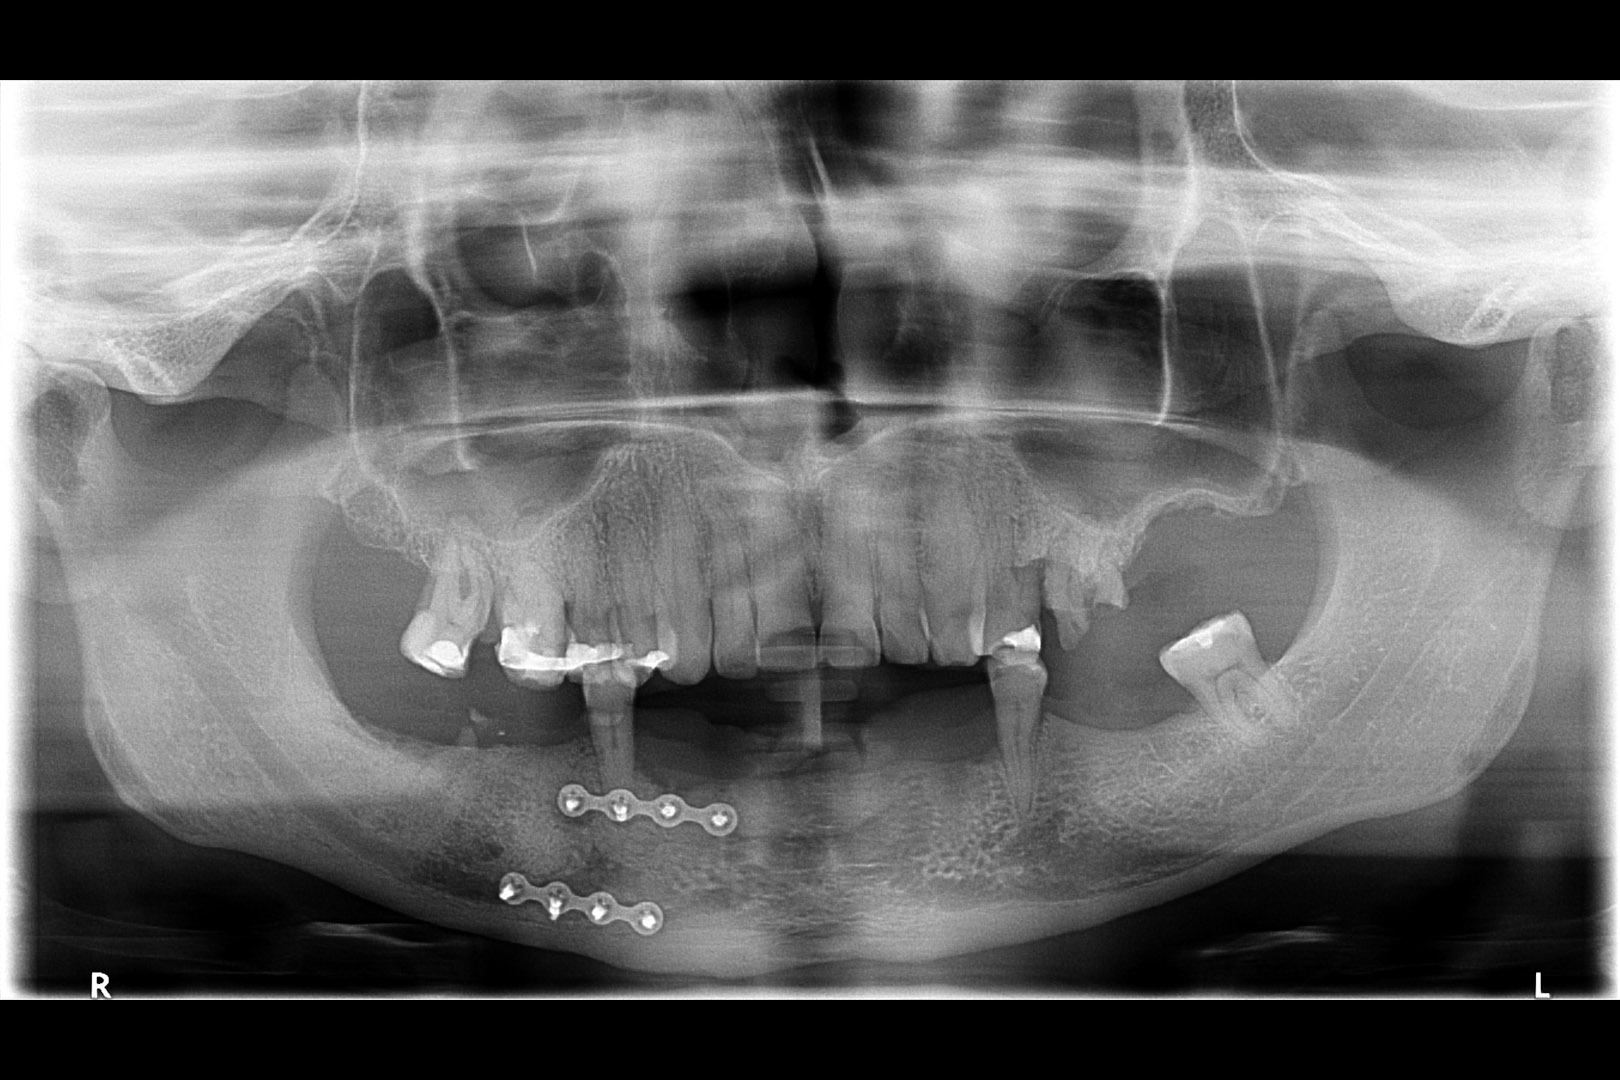

Przed podjęciem leczenia należy określić stopień zaniku kości szczęk oraz żuchwy. W tym celu przeprowadza się badanie kliniczne oraz odpowiednią diagnostykę obrazową pacjenta. Uwzględnia ona zdjęcie panoramiczne OPG jako podstawę dwuwymiarowego obrazowania podłoża kostnego oraz możliwe jest badanie tomograficzne CT lub bardziej precyzyjna tomografia stożkowa CBCT. Opcjonalnie wykorzystywana diagnostycznie tomografia pozwala na bardziej wnikliwą ocenę stopnia zaniku kości w trójwymiarowym, przestrzennym obrazie.

Ta szczególna metoda używana jest w obszarze dolnego łuku zębowego w sytuacji braku dostatecznej ilości kości na wysokość. Metoda stosowana jest w sytuacji rozległych zaników kostnych w bocznych odcinkach żuchwy, w której wprowadzenie implantów groziłoby uszkodzeniem gałązek nerwowych nerwów zębodołowych dolnych. Gałązki nerwowe biegną wraz z naczyniami krwionośnymi we wspólnej pochewce w kanałach kostnych, umieszczonych symetrycznie po obu stronach w trzonach żuchwy.

Technika polega na chirurgicznym ich przemieszczeniu, a przez to stworzeniu bezpiecznego miejsca dla wszczepienia implantów o odpowiednej długości, co gwarantuje ich stabilną pozycję. Stosuje się ją wraz z zabiegiem rekonstrukcji kostnej przy użyciu biomateriałów w formie granulatu i membran. Zabieg ten stosowany jest rzadko, jako alternatywa rozległych regeneracji kostnych. Wybierany bywa jako alternatywa operacyjna tylko w sytuacji, gdy konwencjonalne metody odbudowy kostnej są niewystarczające lub generują ryzyko braku skutecznej odbudowy kostnej celem wszczepienia implantu.

Nasza klinika szczyci się tym, że dr Witkowski opracował własną technikę zabiegu transpozycji nerwów zębodołowych, która prezentowana była na Konferencji Towarzystwa Piezosurgery we Florencji w 2013 roku.

Metoda rekonstrukcji kostnej w oparciu o indywidualnie drukowane siatki z tytanu dla implantacji wszczepów śródkostnych stosowana jest najczęściej jako dwuetapowa. W pierwszym etapie odbudowywana jest kość, natomiast implanty wszczepiane są po okresie 4–6 miesięcy. Na wgojenie implantów oczekujemy od 4 do 6 miesięcy w zależności od miejsca ich lokalizacji. Siatka tytanowa po spełnieniu swojej funkcji rusztowania dla odbudowującej się kości jest następnie usuwana w dniu wszczepienia implantu. Jeżeli kość spełnia odpowiednie warunki, istnieje możliwość zastosowania modyfikacji siatki tytanowej, która umożliwia jednoczesne wprowadzenie implantów wraz z odbudową kostną. Wariant ten skraca czas od pierwszego zabiegu do wykonania gotowych koron protetycznych na wprowadzonych implantach.